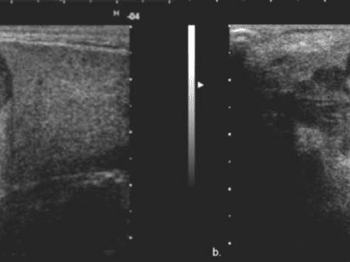

Parotis enfeksiyonlarından en bilineni genellikle çocukluk çağında görülen kabakulaktır. Kabakulak dışında viral ve bakteriyel enfeksiyonlar gelişebilir. Bu durumlarda renkli doppler ultrason tanı açısından önemlidir. Parotisin iyi ve kötü huylu kitleleri mevcuttur. Ultrason incelemesinde parotis kitlesinin şekli, anatomik özellikleri ve doppler inceleme özelliklerine bakılarak tanıya yardımcı olunabilir. Eğer kitle kötü huylu olma potansiyeli taşıyorsa ultrason eşliğinde ince iğne aspirasyon biyopsisi ile patolojik tanı konulabilir. Bir diğer parotis kitlesi sebebi de parotis içinden gelişen lenf nodlarıdır. Genellikle reaktif olan bu lenf nodları (enfeksiyona bağlı) zaman zaman ağrı sebebi olabilir.